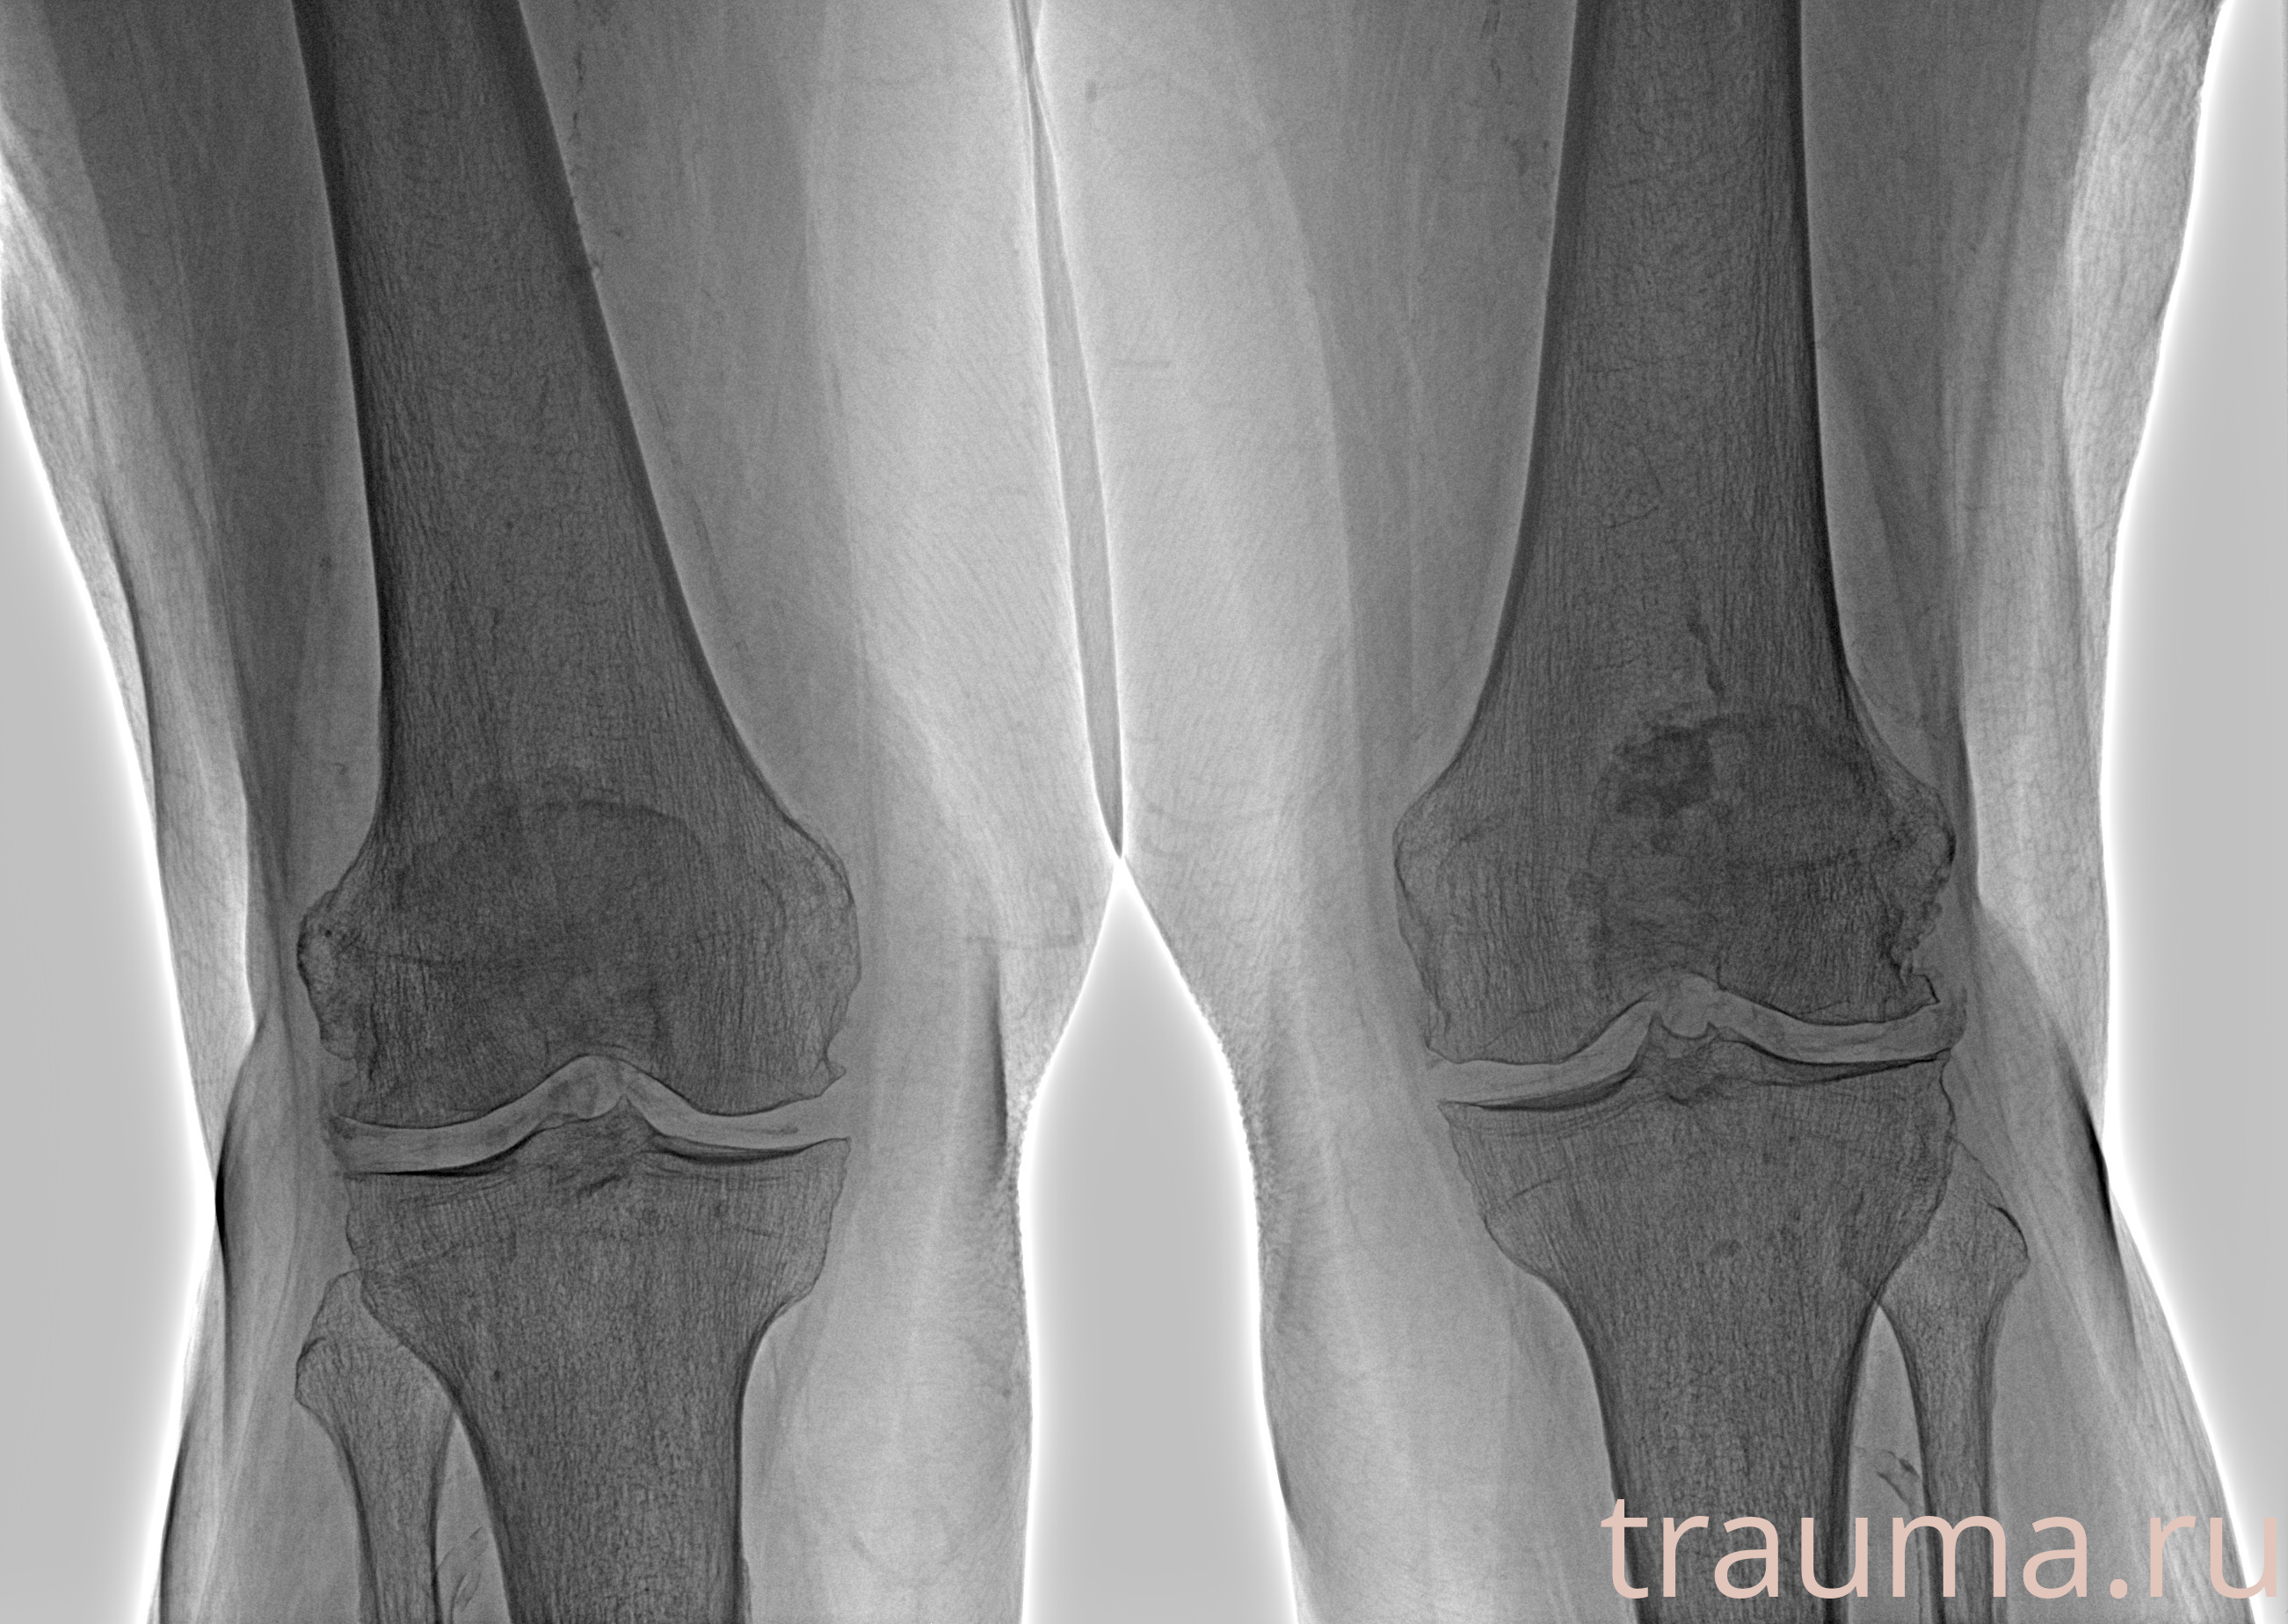

Рентген на дому: по вашему адресу приезжает врач-рентгенолог, травматолог-ортопед с мобильным рентгеновским аппаратом, проводит диагностику травмы или заболевания, делает необходимые рентгенограммы, дает рекомендации по дальнейшему лечению. Получить качественные снимки в домашних условиях возможно благодаря уникальной методике, разработанной МосРентген Центром для института  Склифосовского